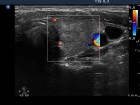

Follow-up examinations (rows from 1st to 8th):

2. Note the relation between volume, echogenicity, vascularization and hormone levels.